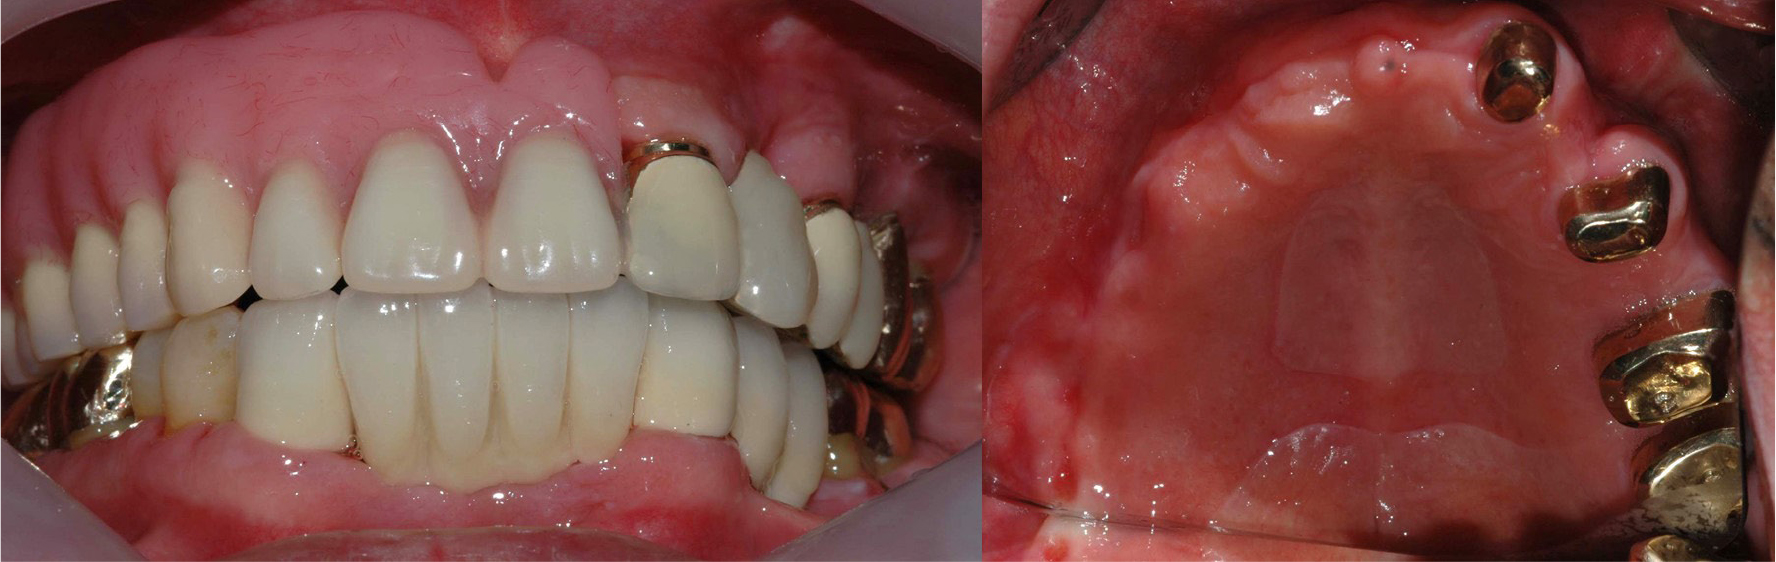

A 62-year-old male patient visited our clinic complaining of increased tooth mobility, gingival recession, and difficulty in mastication in October 2004 (Fig. 1). After clinical and radiographic examination, the maxillary and mandibular teeth with poor prognosis were extracted, and intensive periodontal treatment was performed on the remaining dentition. Through detailed prosthetic consultation with the patient, a conus double-crown-retained RPD using gold alloy for the inner and outer crowns was selected for the maxilla, while a fixed prosthetic denture was chosen for the mandible. The maxillary left lateral incisor, first premolar, first molar, and second molar were used as abutments for the conus double-crown denture. The prostheses were delivered in February 2005 (Fig. 2).

During follow-up appointments, the patient reported a gradual retention loss of the maxillary conus double-crown denture. After 12 years, due to loss of retention, the patient needed a new prosthesis. Clinical and radiographic examinations revealed a severe bone loss in tooth #26 with grade 3 mobility (Fig. 3).